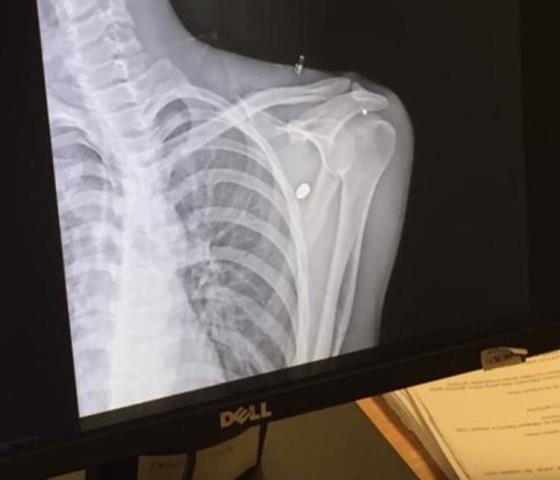

Özellikle yaz aylarında düğün ve eğlence magandalarının silahından çıkan kurşunlar her geçen gün birini yaralamaya veya ölümüne denen oluyor. Geçtiğimiz Perşembe günü yine bir magandanın silahından çıkan yorgun kurşun 20 yaşındaki Mehmet Dündar’ın sol omuzuna isabet ederek akciğere yakın bir yerde kaldı.

29 Ağustos Perşembe Kule Site çivarlarında olduğunu söyleyen Mehmet Dündar olayın kendisinde şok etkisi yarattığını söyledi. Yorgun merminin kendisine isabet ettiğini söyleyen Dündar, “Perşembe günü kuzenim ile bir bankadan çıkıp Kule Siteye doğru gidiyordum. Bu esnada aniden sol omzumda bir acı hissettim. Kuzenimin bana şaka yaptığını söyleyerek neden vurduğunu sordum. Kuzenim bana vurmadığını söyleyerek sol omzumu açtığında kan gördüğünü söyledi. Bunun üzerine hemen 112 arayarak ambulans çağırdık. Hastanede bana bir merminin isabet ettiğini ve merminin kürek kemiği ile akciğer arasında durduğunu söylediler. Doktorlar merminin çıkartılmasının riskli olduğunu söylediler. Tedavim sonrası hastaneden taburcu oldum. Omuzuma gelen merminin nereden geldiğini bilmiyorum. Yaralanmama sebep olan mermiyi ateşleyen şahsın tespit edilmesi halinde şikâyetçiyim” dedi. Mehmet Dündar, bu tür vakaların sık sık yaşandığını, ölümlü ve yaralanmalı olaylarla sonuçlanan bu durumların durdurulmasını istediğini söyledi.